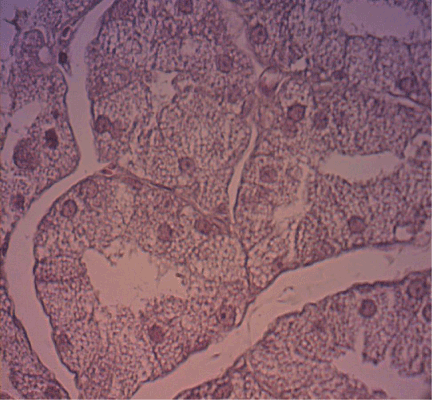

Figure 1. The parotid salivary gland of Wistar rats at 51 days: saline solution. The acini and parenchyma showing a normal acinar architecture, no increase in volume and number of acini. (HE; 40 X magnification).

Figure 2. The parotid salivary gland of Wistar rats at 51 days: lithium. The acini and parenchyma with normal acinar architecture, showing that there was no increase in the volume and acinar cell number. (HE; 40 X magnification)